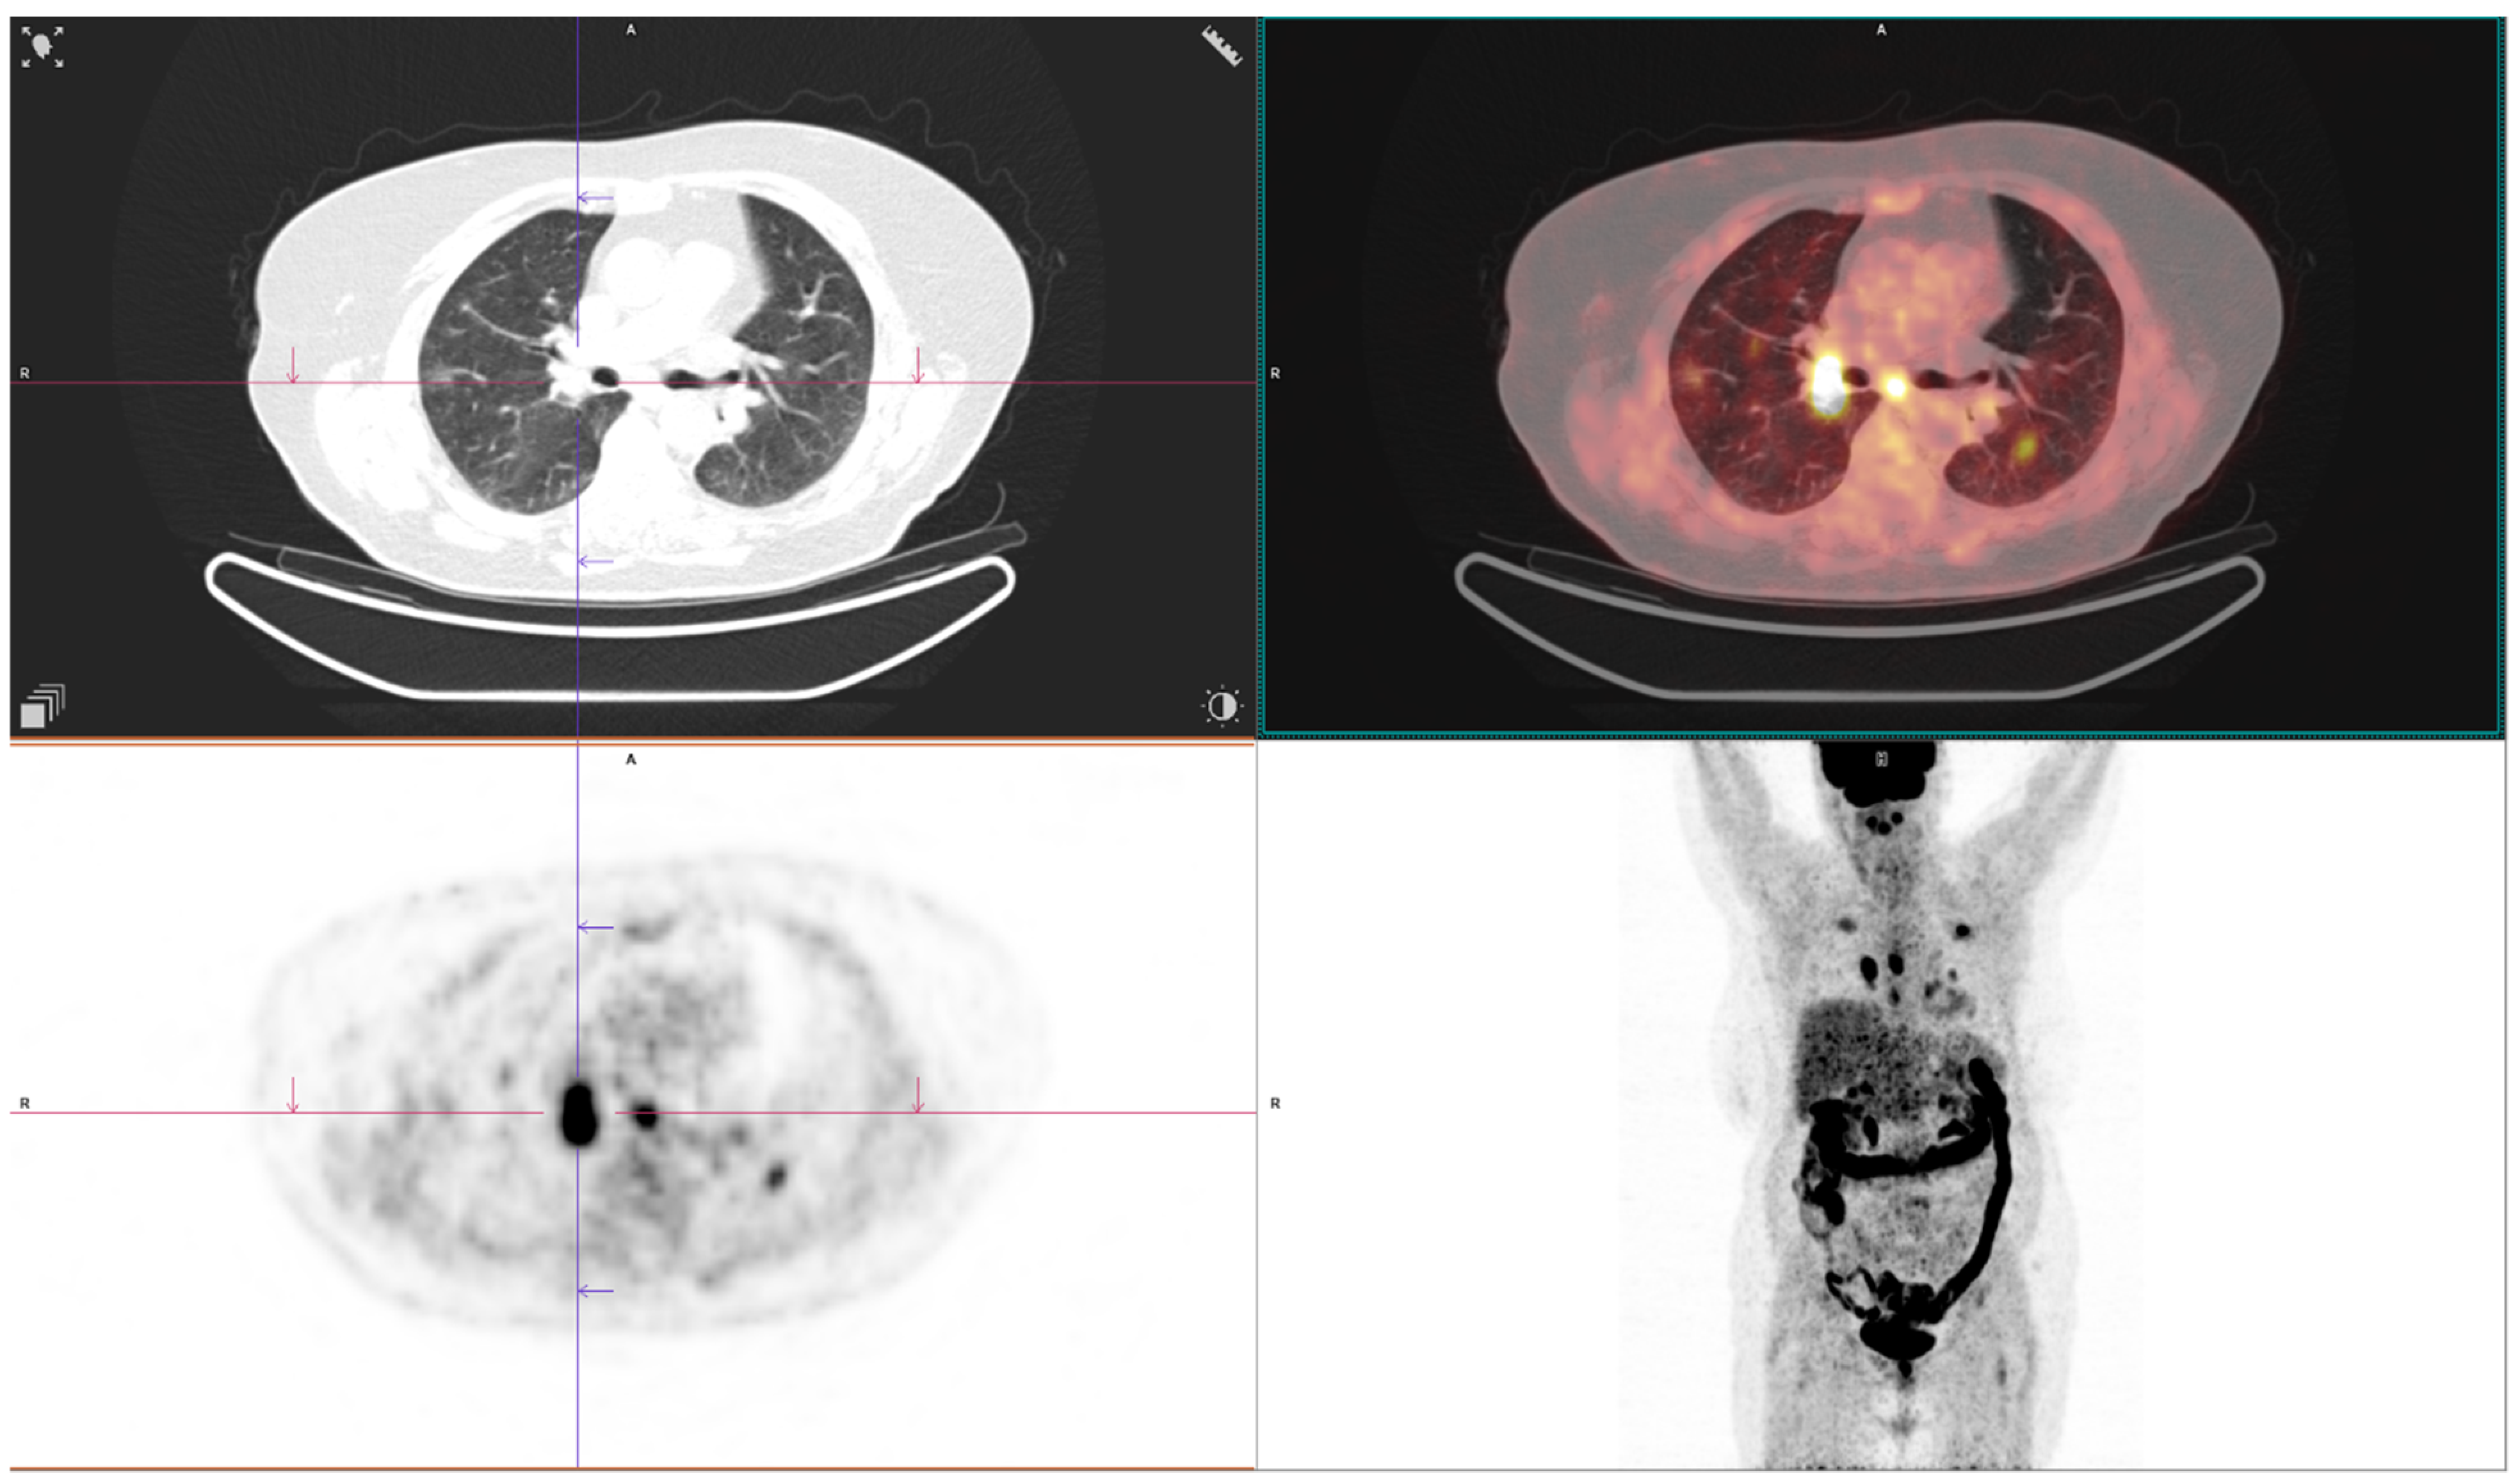

3. Results

| Acinar | Papillary | Lepidic | Solid | AIS-MIA | Overall p Value | Comparison Group | Mean Difference | 95%CI ** | Post Hoc p Value ¥ | |

| Metastases present, n (%) | 3 (9.4%) | 7 (25.0%) | 0 (0.0%) | 8 (61.5%) | 0 (0.0%) | <0.001 | Acinar vs. solid | na | na | 0.001 |

| Lepidic vs. solid | na | na | <0.001 | |||||||

| Solid vs. AIS-MIA | na | na | 0.003 | |||||||

| SUVmax, mean ± SD | 4.9 ± 1.1 | 5.3 ± 1.3 | 5.1 ± 0.7 | 6.3 ± 0.8 | 3.3 ± 0.8 | <0.001 | Acinar vs. solid | −1.35 | −1.89 to −0.76 | 0.001 |

| Acinar vs. AIS-MIA | 1.65 | 1.00 to 2.28 | <0.001 | |||||||

| Papillary vs. AIS-MIA | 2.01 | 1.35 to 2.72 | <0.001 | |||||||

| Lepidic vs. AIS-MIA | 1.83 | 1.23 to 2.38 | <0.001 | |||||||

| Solid vs. AIS-MIA | −3 | 2.32 vs. 3.59 | <0.001 |